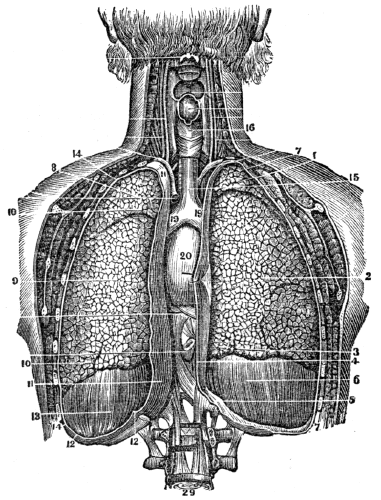

| 23. | Anatomy of the Respiratory Organs, | 209 |

| 24. | Physiology of the Respiratory Organs, | 217 |

| 25. | Hygiene of the Respiratory Organs, | 228 |

| 26. | Hygiene of the Respiratory Organs, continued, | 239 |